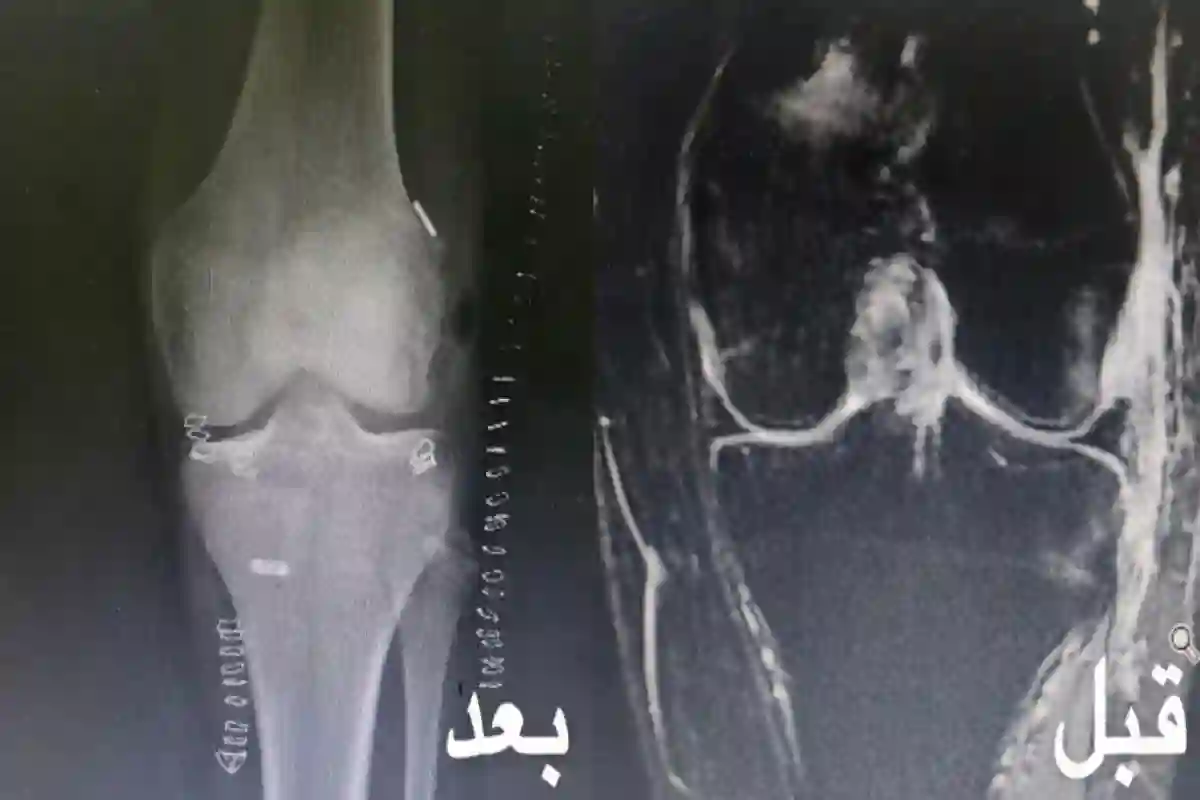

"سعود الطبية" تنجح في إجراء عملية جراحية دقيقة تعيد لمصاب القدرة على الحركة بعد إصابة بليغ

استشاري جراحة مفاصل ينصح مرضى خشونة الركبة بإجراء عملية تبديل المفصل.. ويكشف نسبة نجاحها